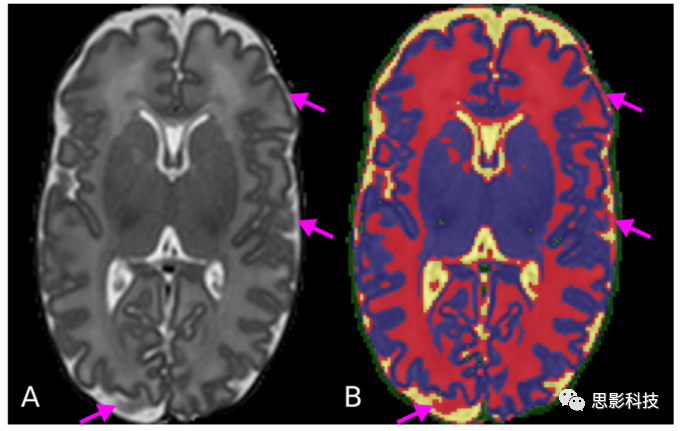

c) CSF-WM 部分容積(PV)效應(yīng)。胎兒/新生兒MR圖像與成人圖像相比,表現(xiàn)為反轉(zhuǎn)的WM(白質(zhì))/GM(灰質(zhì))強度對比。WM在圍產(chǎn)期腦內(nèi)無髓鞘,在T2加權(quán)像上比GM更亮,而在成人圖像上GMWM具有更大的強度值。CSFGMCSF-CGMCGcortical GM邊界上的混合導(dǎo)致了其與WM相似的強度(見圖3)。這種PV效應(yīng)導(dǎo)致了CSF-CGM界面將PV(部分容積)體素錯誤地標(biāo)記為WM。

3所示。CSF-WM 部分容積效應(yīng)明顯存在于CSF-CGM邊界。新生兒T2 MR圖像(A)分為不同的組織類型(黃色:CSF,紅色:WM,藍(lán)色:GM,綠色:背景) (B)箭頭所指的區(qū)域是CSFCGM的部分容積,使得其強度與WM的強度相似。